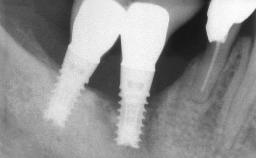

Oral implants are highly successful and offer long-term benefits, especially in the rehabilitation of edentulous patients or patients with oral defects following ablative tumor surgery (Albrektsson and coworkers 1986), and also after radiation therapy (Schiegnitz and coworkers 2014). With the number of implants placed globally going into the millions, implant dentists have observed some rare adverse events. Although carcinogenesis around implants is an exceedingly rare phenomenon, we recently reported about 15 patients treated for carcinomas adjacent to implants at our clinical department over a period of fifteen years (Moergel and coworkers 2014). The following case represents a patient of this cohort; it discusses possible risk factors and makes suggestions for a recall schedule. A 70-year-old woman was referred to our outpatient department for evaluation of a rapidly growing macroscopic alteration of the mucosa in the left mandible.

# of Implants 4

Type of Implants One-Piece